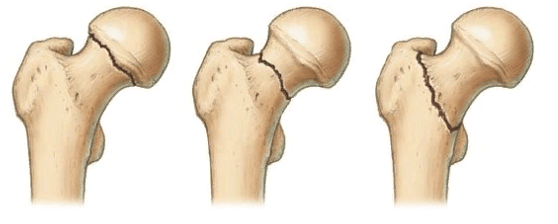

Выделяют несколько разновидностей переломов:

Тип 1: абдукционный, субкапитальный, неполный перелом без смещения. Происходит он вследствие действия отводящих натяжений. Шейка и диафиз бедра при переломе направлены в сторону головки. Костные фрагменты крепко вклинены, и линия поверхности перелома приближена к горизонтальной. Нарушение кровоснабжения минимальные (до 10,2%). Прогноз на выздоровление хороший.

Слева-направо: субкапитальный, трансцервикальный, базисцервикальный переломы.

Тип 2: аддукционный, субкапитальный, полный перелом без смещения. Перелом расположен в вертикальной плоскости, проходит через шейку бедра. Трабекулы и нижний корковый слой разорваны, без смещения. Микроциркуляция нарушена на 23,6%. Прогноз благоприятный.

Тип 3: аддукционный перелом с неполным смещением костных структур. Он характерен варусной деформацией шейки бедра, но фрагменты остаются соединенными за счет задне-нижнего блока. Дистальный костный фрагмент – в положении наружной ротации и отведения с углом, открытым кпереди. Имеется оскольчатый перелом задней поверхности шейки. Трабекулы и нижний кортикальный слой разорваны. Нарушение васкуляризации достигает 42,8%. Риск развития асептического некроза.

Тип 4: аддукционный перелом с полным смещением. Головка лишается всех связей с синовиальной оболочкой капсулы, в результате чего фрагмент становится свободным. Нарушение кровоснабжения максимальное (54,4%). Риск образования асептического некроза повышенный.